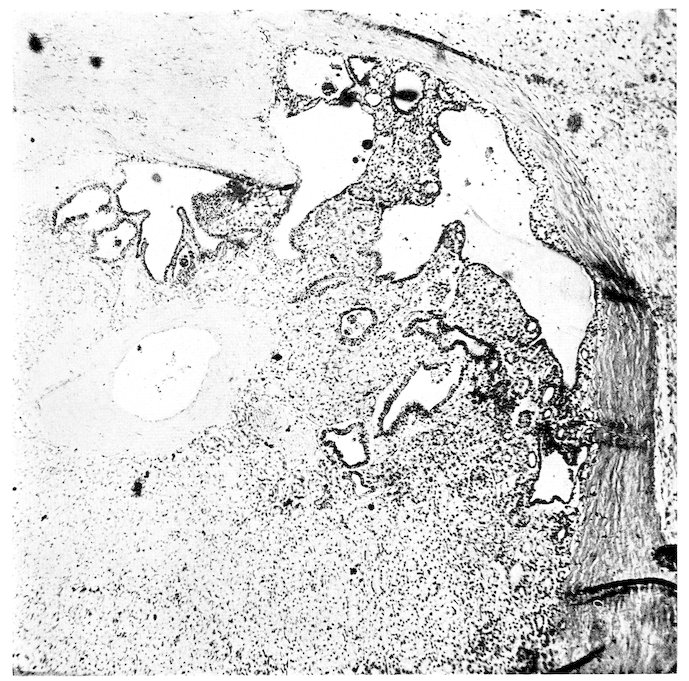

Columbæ:

Columbidæ:

Ocyphaps lophotes,